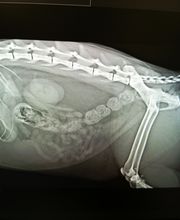

Benvenuti a CASTELVET: La Nostra Storia e Passione per la Cura degli Animali Formazione e Esperienze Professionali Il dottor Pier Luigi Faraglia si è laureato presso la Facoltà di Medicina Veterinaria dell'Università di Bologna. Con una solida base accademica, un percorso professionale di alto livello, collabora con enti rinomati, come lIstituto Nazionale per la Fauna Selvatica. Un iter lavorativo di 30 anni. Dal dicembre 2024, è Direttore Sanitario e unico responsabile di CASTELVET. Ambiti di Specializzazione e Approccio Professionale Il Dott. Faraglia si occupa di un ampio ventaglio di discipline veterinarie: medicina generale, interna e preventiva (profilassi vaccinale, malattie infettive e parassitarie); dermatologia, pronto soccorso, diagnostica, analisi cliniche, chirurgia, nutrizione e comportamento animale. In ambito dermatologico, una vasta esperienza: ha collaborato con specialisti, seguito corsi avanzati, affinando diagnosi e trattamento di patologie cutanee del cane e del gatto, che gli è valsa una collaborazione con lIstituto Superiore di Sanità. Un approccio diagnostico con massima attenzione ai dettagli: unanamnesi completa attraverso un dialogo approfondito con i proprietari, cogliendo anche elementi apparentemente insignificanti, per offrire diagnosi accurate e terapie personalizzate. Un Approccio Pratico e Professionale - Passione e Dedizione Alla base vi è una filosofia pragmatica e rispettosa: ogni decisione è presa nel migliore interesse dellanimale, ascoltando il proprietario e guidandolo verso scelte consapevoli e scientificamente fondate. CASTELVET : Una Visione Innovativa della Veterinaria CASTELVET non è solo un luogo di cura, ma un punto di riferimento per prevenzione, trattamento delle patologie animali e offrire soluzioni efficaci e rispettose del benessere.